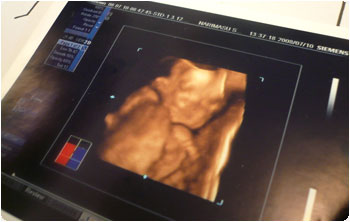

日本にいる間に、母親にエコー検査の様子を見て欲しいと思っていて、それなら、最新の4Dとやらをやってみようという事になりました。シドニーにもあるのですが、日本で6,000円の所を、あっちでは250ドル以上するのです・・・。

母親の英会話のお友達が産婦人科に勤めているという事で、予約を取ってくれたので、そこまで行って受けて来ました〜!が!!やっぱり、いつもの事なのですが、息子は両手を顔で覆って、プイと私の背骨の方を向いている・・・。

おーい!こっちを向いておくれ〜!技師さん泣かせは、シドニーでもこっちでも一緒だったか・・・。しばらく待ってみましょう、と一旦休憩した後で再開してみると!あ!こっち向きました!でも・・・。こ・・・怖い。何故って、こっちを向いたものの、胎盤にムギューッと顔を押し当てていたんですって。で、唇の感覚はもう発達しているらしく、その感触に反応して唇をパクパクさせておりました。まぁ、こんな感じで十分満足であります。とりあえず人間ぽい感じだけは分かったので・・・。アハハ。なんとなーく、マイケル似の子な予感。それは大歓迎です。

いやぁーー、こんなんがお腹の中で育ってる最中で、ボカボカ暴れてるんだなぁ。不思議なものですわ。

男の子だという事は再確認したので、私たちの息子の名前はKenに決定です。当て字にした感じの名前にはしたくないし、(十夢・トムとか、聖韻・セインとか)英語名と日本語名を2つ持つのはややっこしいし。英語にあって日本語にない音が入ってるのも嫌だし(これでかなり減ってしまった)。何と言っても、ハーフとはいえ、バリバリアジア人の見た目の子なので、オーストラリアでアジア人が英語名を名乗るのは普通だけど、日本ではねぇ・・・。という訳で、英語圏でも日本にもある名前・・・で、Kenになりました。